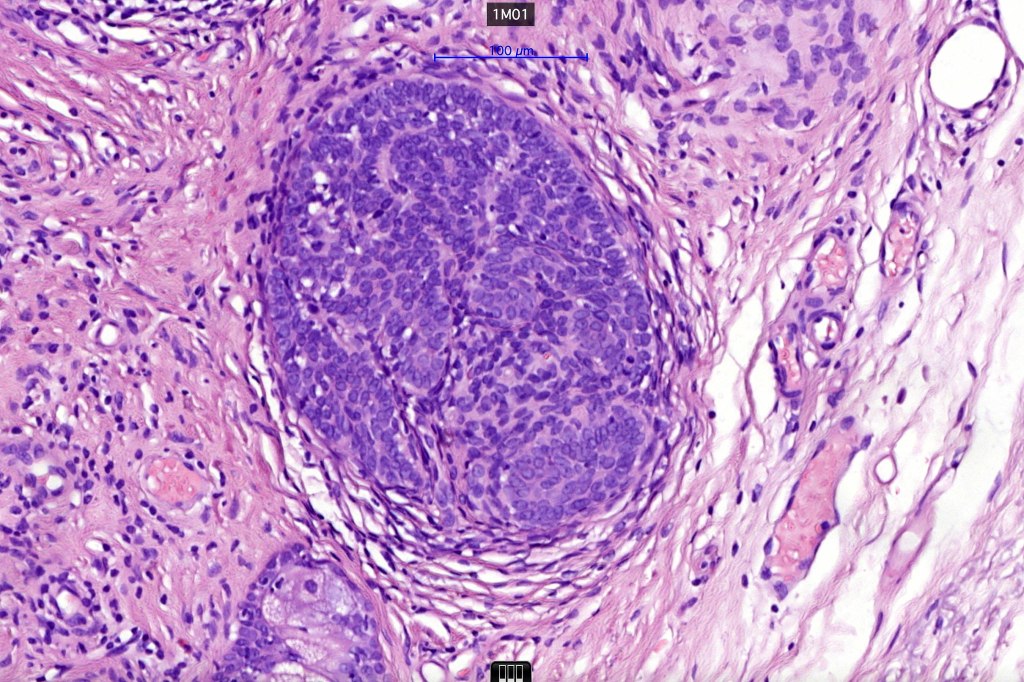

•The classical appearance consists of keratocysts & lobules of basaloid cells

•Basaloid lobules show peripheral palisading

•Perifollicular mesenchyme is always conspicuous and sometimes densely aggregated are seen indenting the baslaloid lobules (papillary mesenchymal bodies)

Trichoepithelioma should be distinguished from trichoblastoma since the latter is very rarely syndromic. Trichoepithelioma is largely a dermal tumor whereas trichoblastoma often extends from the dermis into subcutaneous fat or deeper in very large examples. Papillary mesenchymal bodies are much better formed and generally more obvious in trichoepithelioma. Trichoepithelioma must also be distinguished from basal cell carcinoma. Retraction artifact & stromal mucin are features of basal cell carcinoma and not trichoepithelioma. Papillary mesenchymal bodies are not seen in basal cell carcinoma.